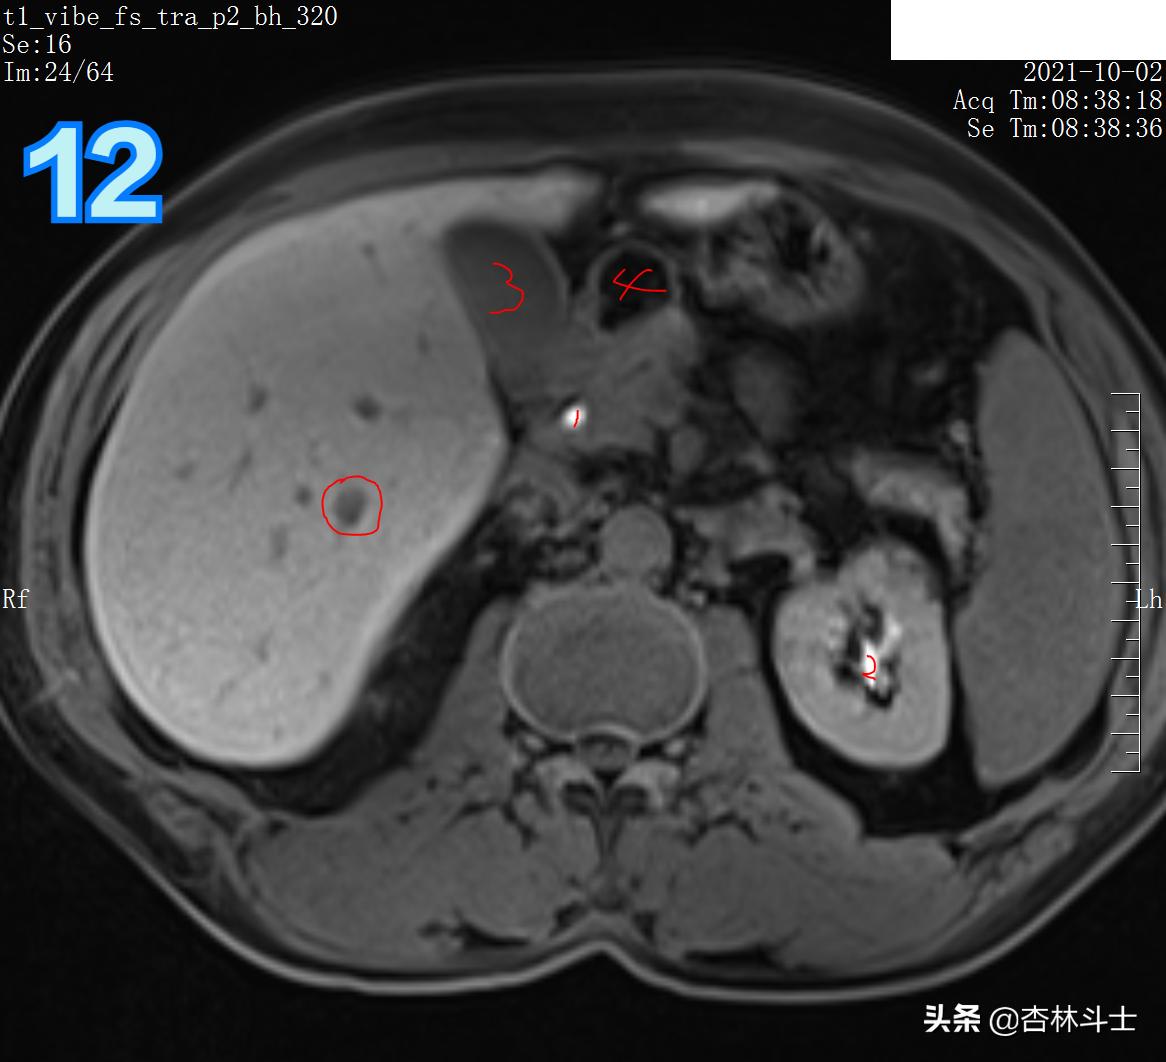

T1加权压脂

图9 蓝框为血管 红框为病灶,病灶在门静脉期呈等略低信号。蓝框血管目的为方便定位新发病灶。

T1加权压脂平衡期

图10 红框病灶对比剂进一步廓清,呈略低信号。图中1、皮下脂肪 2、胆囊 3、胃腔 4、左肾 5、脾脏 6、脊柱 7、腹主动脉 8、下腔静脉 9、胰头 10、背部肌肉(竖脊肌)11、腰大肌 12、腹壁肌肉(腹外斜肌、腹内斜肌、腹横肌)